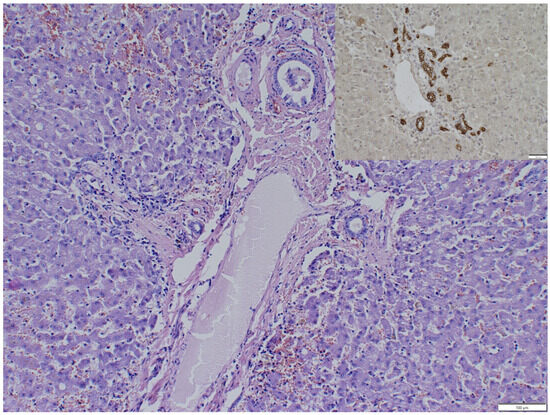

An Incidental Necropsy Finding: Intrathoracic Ectopic Liver in a Cat

Ectopic liver is a rare anomaly characterized by the presence of hepatic tissue outside its normal anatomical location without continuity with the main liver. Reports of this condition are sporadic in human medicine, and cases in veterinary species remain limited. This condition may [...] Read more.

Ectopic liver is a rare anomaly characterized by the presence of hepatic tissue outside its normal anatomical location without continuity with the main liver. Reports of this condition are sporadic in human medicine, and cases in veterinary species remain limited. This condition may arise as a congenital developmental defect or as a consequence of prior traumatic injury leading to fragmentation and displacement of hepatic tissue. This case study describes an incidental intrathoracic ectopic liver identified in a 6-year-old male cat that died of acute suppurative bacterial pneumonia. Necropsy revealed a well-demarcated, encapsulated, large mass within the middle of the caudal mediastinum, unattached to the diaphragm, lungs, or pericardium. Cytologic and histopathologic examinations confirmed the presence of hepatic tissue with preserved lobular architecture. No evidence of previous trauma or diaphragmatic defects was present, supporting the congenital origin. The accompanying severe bacterial pneumonia was unrelated to the mediastinal mass. This study highlights the diagnostic challenges associated with intrathoracic ectopic liver, which can mimic neoplastic or inflammatory masses. Awareness of this entity is essential for accurate diagnosis. Given the documented risk of malignant transformation in ectopic hepatic tissue, surgical excision and histopathological assessment should be considered whenever such lesions are detected. Full article